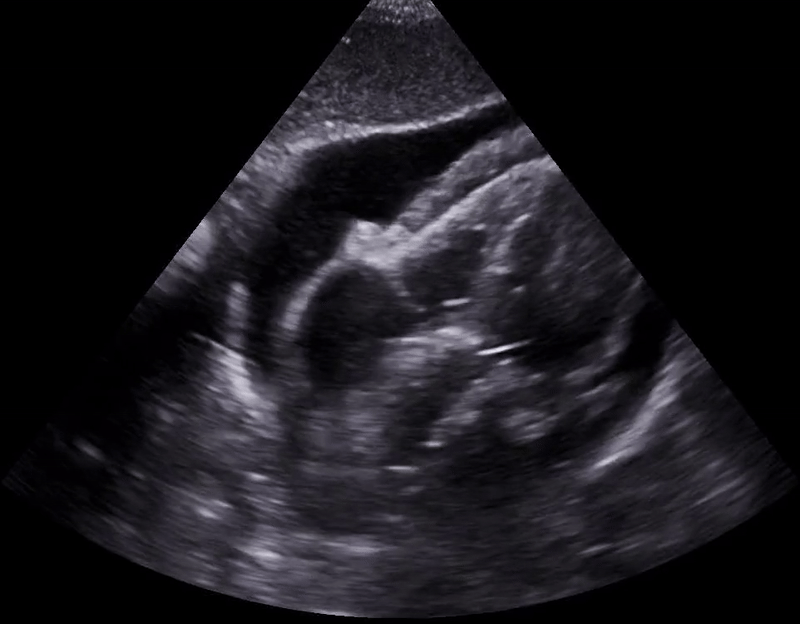

Plethoric IVC.

POCUS cardiac: You won’t diagnose cardiac tamponade unless you look, so that’s the biggest take home point, please just get up and look. Once you’re on your feet with ultrasound probe in hand, a plethoric IVC is the most sensitive finding, and diastolic right ventricular collapse is the most specific finding. In the above clips, you are visualizing obstructive shock. When the heart relaxes and tries to fill during diastole, it cannot because of the pressure applied on the right ventricular free wall by the pericardial effusion.